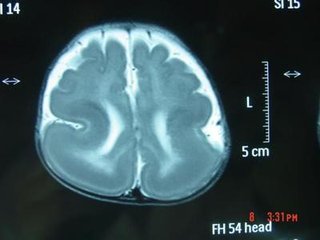

巨脑回的CT表现为:显示大脑半球皮质明显增厚,脑白质减少,脑沟变深多发生在额顶叶附近的蛛网膜下腔增宽病侧脑室扩大

MR表现为受累侧大脑半球中到重度增大;皮质发育不良,脑回宽,脑沟浅,皮层增厚;白质信号不均匀,提示灰质异位和发育不良的神经元和胶质。